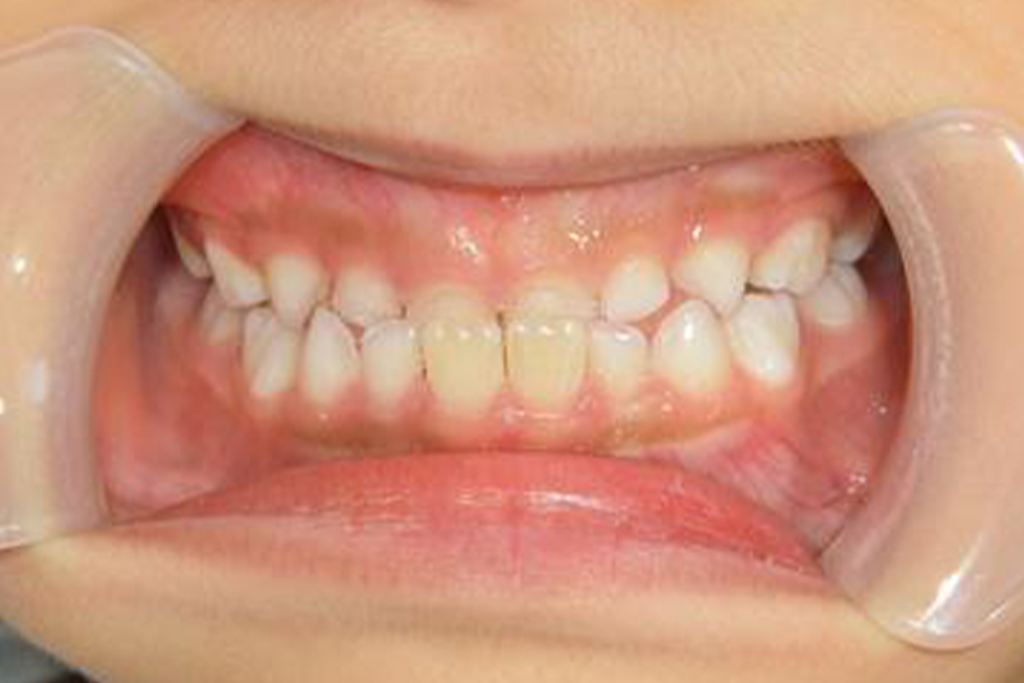

●治療前

●5ヶ月後(現在治療中)

| 診断 | 前歯部反対咬合 |

|---|---|

| 初診時の 年齢 | 6歳 |

| 治療内容 | プレオルソ |

| 治療期間 | 2021年4月~現在継続中 |

| 治療総額 | 88,000円(※症例により異なります) |

| 治療の メリット | 正常咬合、鼻呼吸への誘導、お口ポカンの改善 |

| 治療の リスク |

嘔吐反射の強い場合、装置を装着できない・装置を装着すると口呼吸ができない |